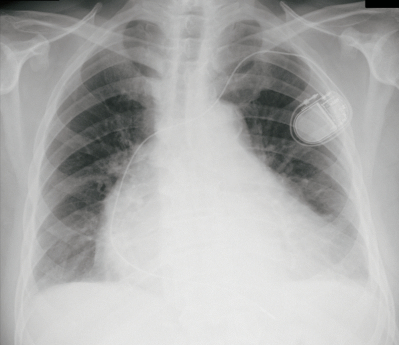

既往歴: 徐脈性心房細動、Ⅰ度の僧帽弁閉鎖不全、心不全、高血圧症で、抗血栓薬とアンジオテンシン変換酵素〈ACE〉阻害薬、利尿薬を内服中である。5年前に徐脈性心房細動に対し、ペースメーカー植込み術を受けた。

心電図及び胸部エックス線写真を別に示す。

c. 心室ペーシング